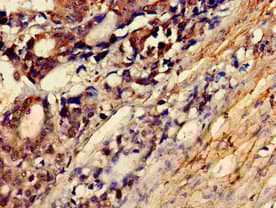

Anti-Myosin light chain kinase/MLCK antibody(ab236299)

Rabbit Polyclonal Myosin light chain kinase/MLCK antibody. Suitable for IHC-P, ICC/IF and reacts with Human samples. Cited in 1 publication. Immunogen corresponding to Recombinant Fragment Protein within Human Myosin light chain kinase, smooth muscle aa 250-400.

Applications ICC/IF, IHC-P